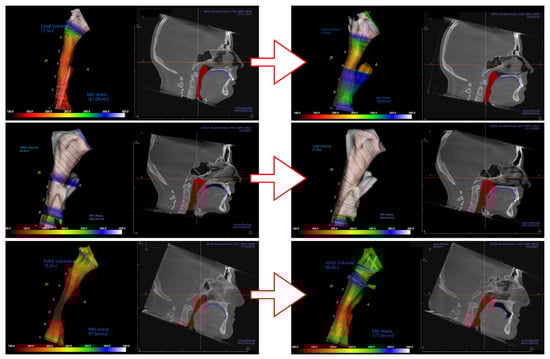

When the software analyzes the input data and evaluates the airway, different colors of the color spectrum illustrate the constriction of the airway. Severe airway obstructions are represented by black, dark red, red followed by orange, yellow and green. The green color categorizes the airway into adequate passage of air followed by blue and white representing the widest airway dimension.

Example of the software 3D evaluation of the airway from the CBCT shows pre-treatment airway constriction (Figure 3a) and post-treatment evaluation after orthodontic therapy (Figure 3b). This example shows rather insignificant improvement of airway constriction as well no significant change of tongue posture (blue).

Figure 3. Examples of CBCT 3D analysis of the airway with evaluation of constriction in the software Invivo 6, from Anatomage (Santa Lara, CA, USA). (a) Pre-treatment CBCT with constriction; (b) post-treatment CBCT analysis with insignificantly improved airway constriction and unchanged tongue position.